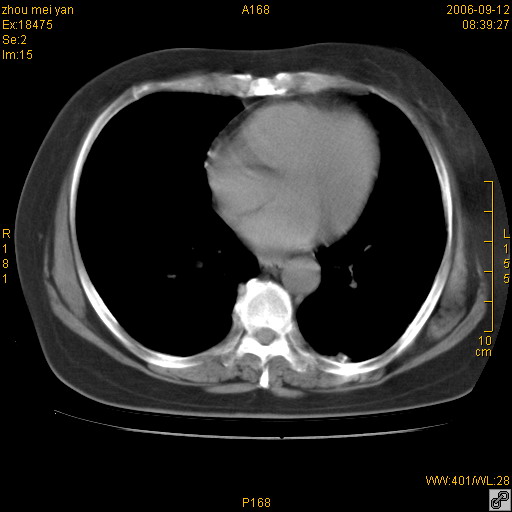

患者、女、55岁。因心率失常住院检查ct发现胸部多发结节。腹部b超肝、胆、胰、脾、肾、子宫附件未见异常。无结核病史,无粉尘接触史。请大家来会诊。谢谢!

病变位于胸膜,多发结节,边界清楚,内见小结节状钙化。其它未见异常。

双侧胸膜多发结节,形态不规则,边缘较清楚,每一个结节中心似乎都有钙化点的特征,与胸膜广基相切。临床无结核病史,无粉尘接触史。

影像表现十分有特点:双侧肋胸膜及膈胸膜广泛散在分布大小在2至6mm左右,较大病灶中心可见钙化。

考虑恶性胸膜间皮瘤可能性大,病灶位于胸膜,以宽基地与胸膜相连,呈结节样改变,部分病灶内可见点状钙化影。请各位老师多多指导!

双侧肋胸膜及膈胸膜广泛散在分布大小不等结节影,较大病灶中心可见钙化。